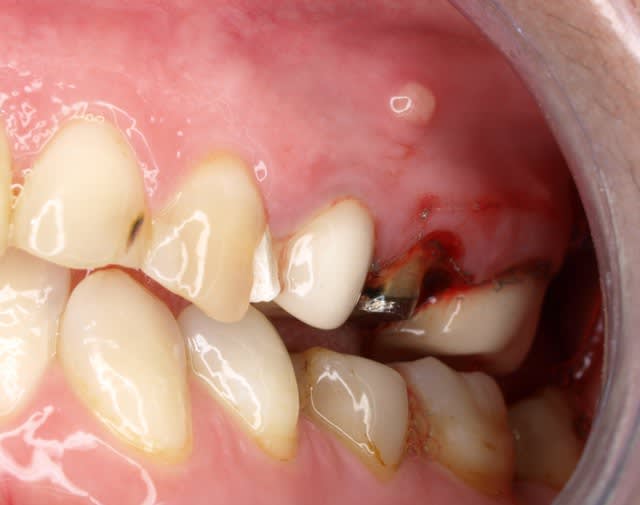

voila une belle indication

1 radio debut m1ld0f - Eugenol

2 depose  bridge p6o8dv - Eugenol

un indice important:

la patiente me dit qu ella a eu mal apres la pose des 3 dents alors que tout allait bien avant . les dents etaient deja devitalisées depuis longtemps...

l absces date de 6 mois.ça suinte tous les jours

vous pensez a quoi?

et a quel traitement ?

Les couronnes semblent solidarisées, non?

La première solution serait de déposer les couronnes, et les inlay core, RTE et pose de 3 couronnes provisoires pendant 6 mois, non solidarisées.

Sondage paro pour être sur que ce n est pas un abcès endo paro...sinon, c est grosso modo cuit pour la prémolaire.

Sur échec de ce traitement, résection apicale ....

Enfin bon, c est le traitement de 1 ère intention en général.

Si dépose des inlay core trop compliqué, recsection apicale en 1 été intention.

Édit: oups, non elles ne sont pas solidarisées , mais ça change pas grand chose pour le traitement de la 25 ou 15.